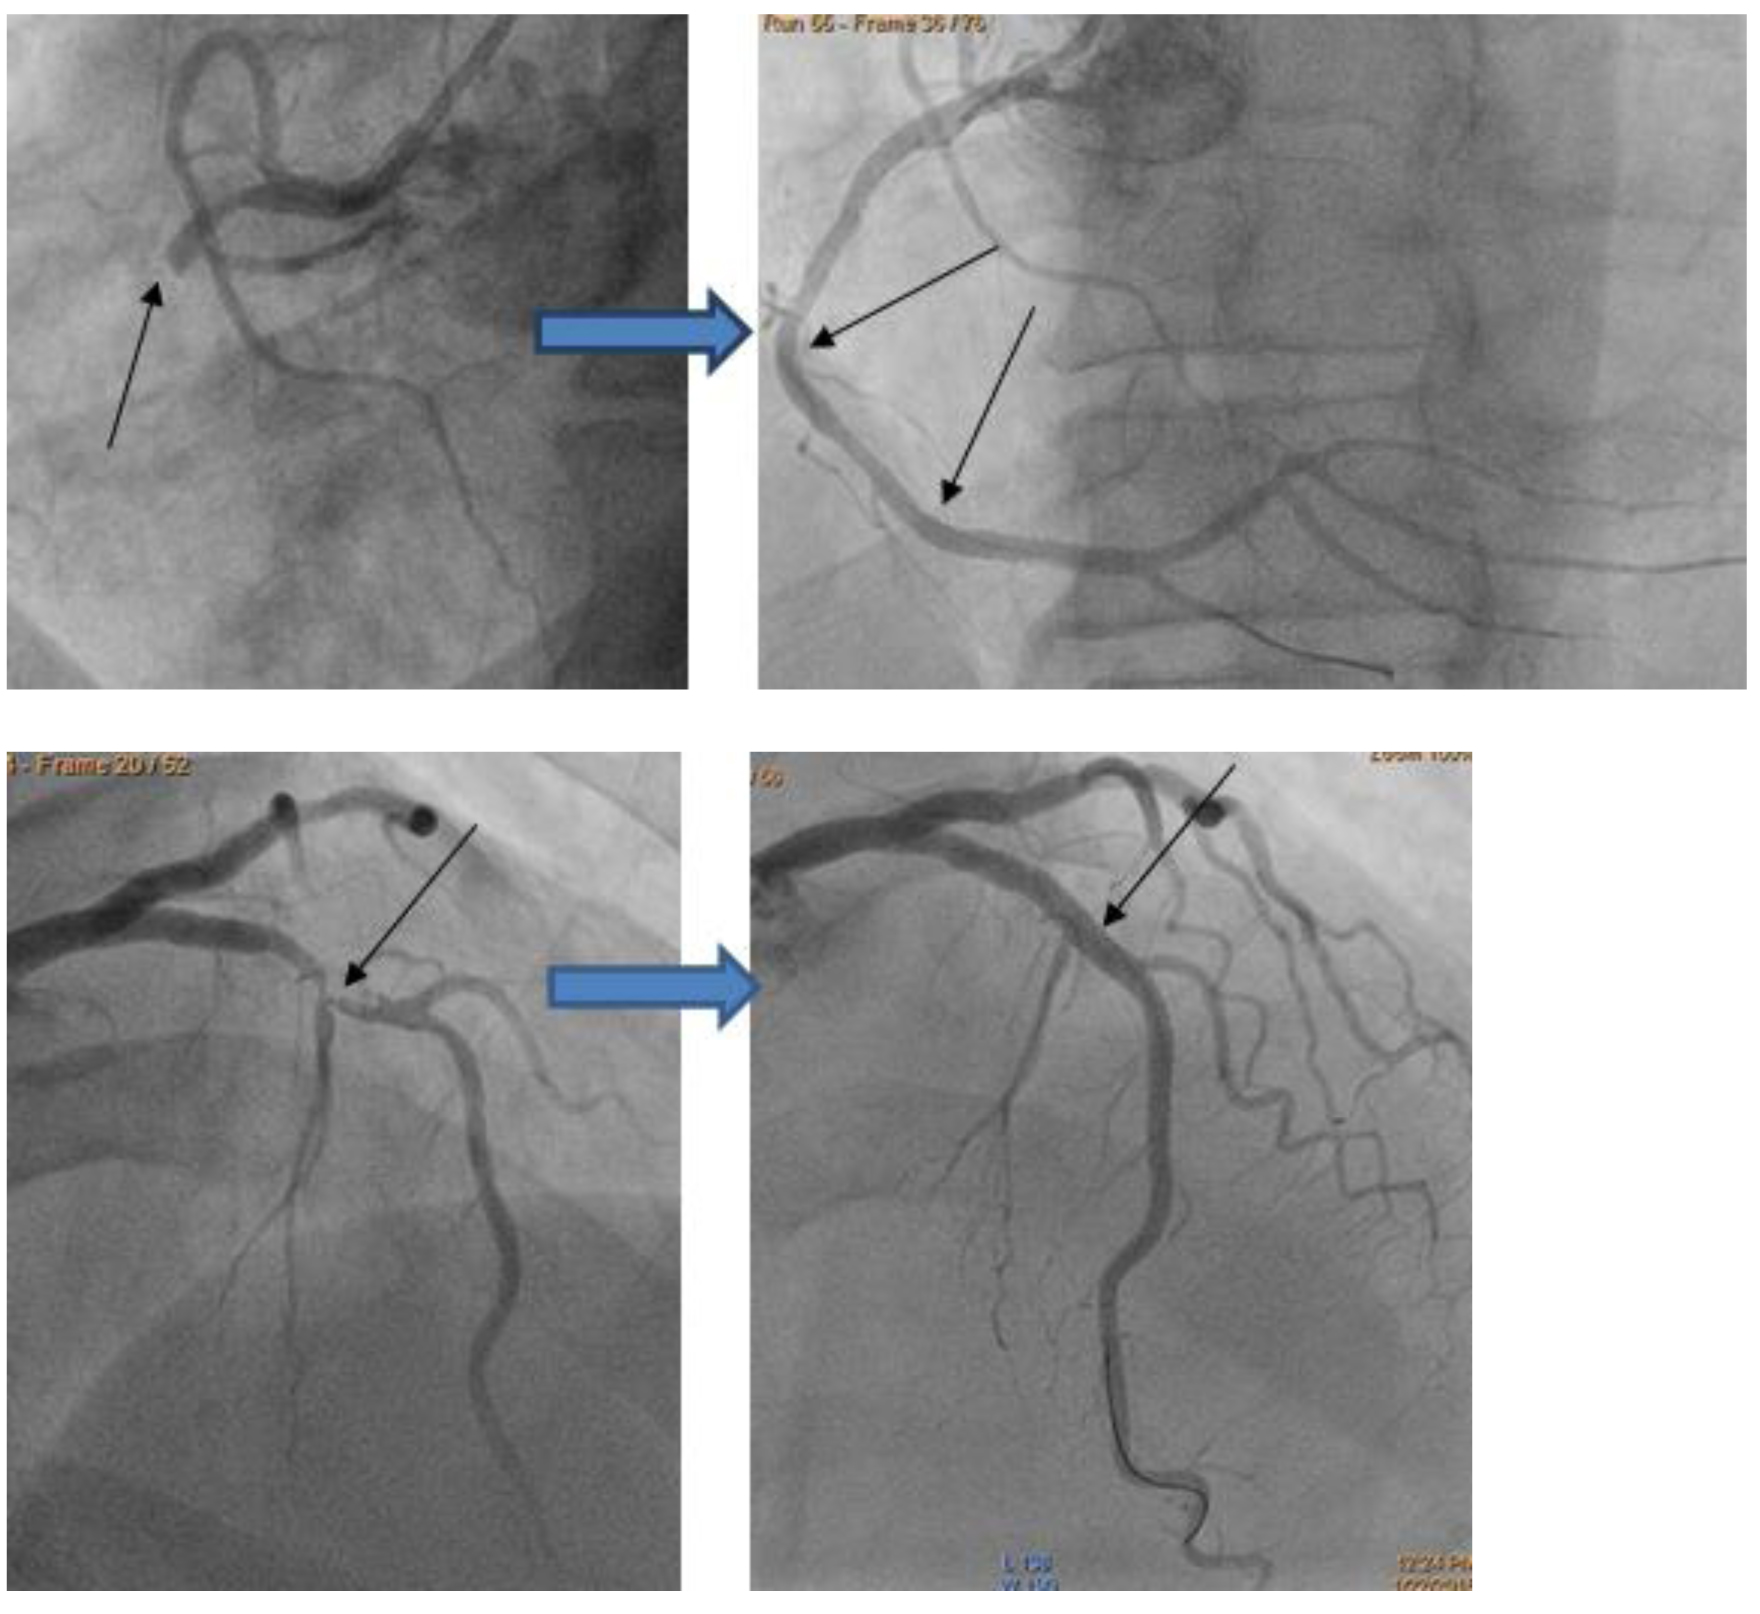

Примеры, где выявлены проблемы, подлежащие оперативному лечению. В данных случаях выполнено одномоментное стентирование (на фото – коронарография до и после стентирования):